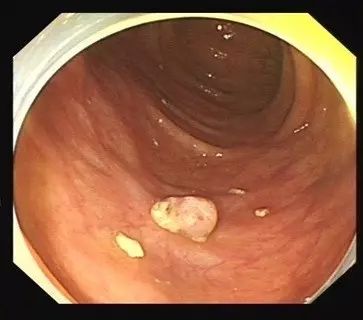

直肠息肉可触及质软且可推移的肿块,指套上常染血,色鲜红。